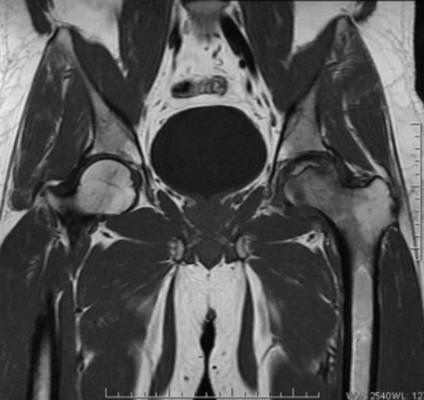

МР-скан коксофеморальных сочленений, вариант нормы

Интерпретацией изображений занимается врач-рентгенолог. В норме на серии томограмм травматических изменений не определяется:

структура костной ткани однородна, без дистрофических признаков;

субхондрального склероза суставных поверхностей нет;

капсула сочленений не утолщена, в полости присутствует небольшое количество синовиальной жидкости с однородным МР-сигналом;

костные крыши вертлужных впадин сформированы правильно, суставные щели равномерные, конгруэнтность (сопоставимость, согласованность) поверхностей сохранена;

целостность связочного аппарата не нарушена;

сигнал хрящевого компонента без особенностей, областей истончения нет;

краевые заострения суставных поверхностей вертлужных впадин отсутствуют;

окружающие мягкие ткани без видимой патологии;

бедренные и тазовые кости в зоне сканирования без очаговых изменений.